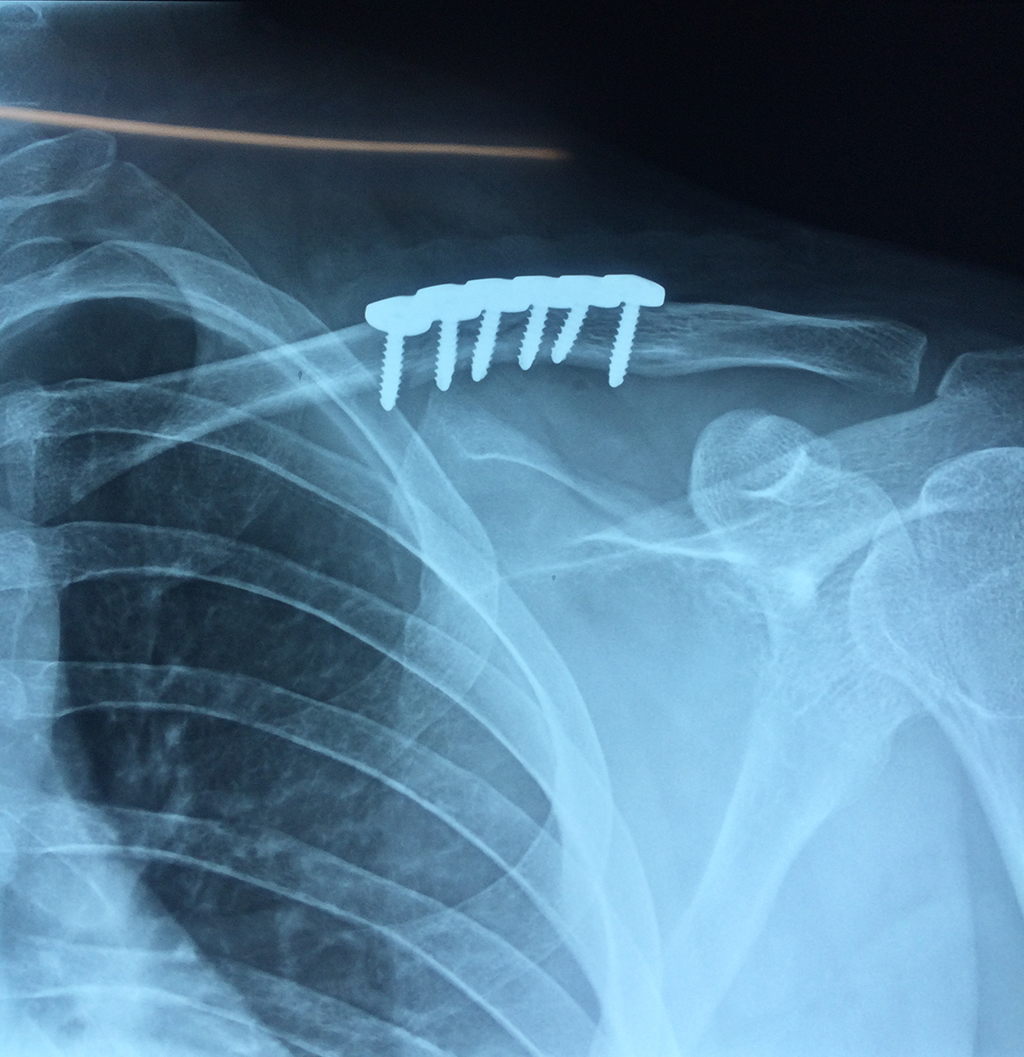

Cirugías de Codos - Clavícula